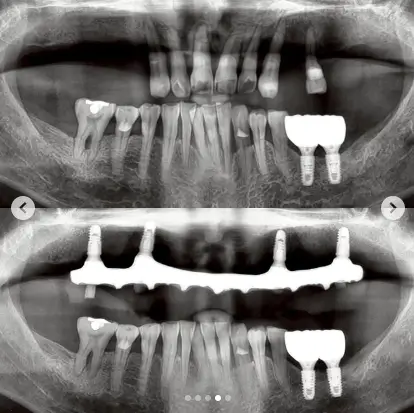

Before Treatment

Before

After Treatment

After

This patient visited our dental clinic in Bangkok with multiple missing teeth that affected both chewing ability and overall appearance. After a detailed 3D CT scan and oral examination, our implant specialist recommended a multiple dental implant treatment plan to restore function and aesthetics.

The procedure involved placing three titanium implant posts in areas with missing teeth, followed by a healing period to allow the implants to integrate with the jawbone. Once healing was complete, custom-made porcelain crowns were attached to the implants, recreating a natural-looking, even smile.